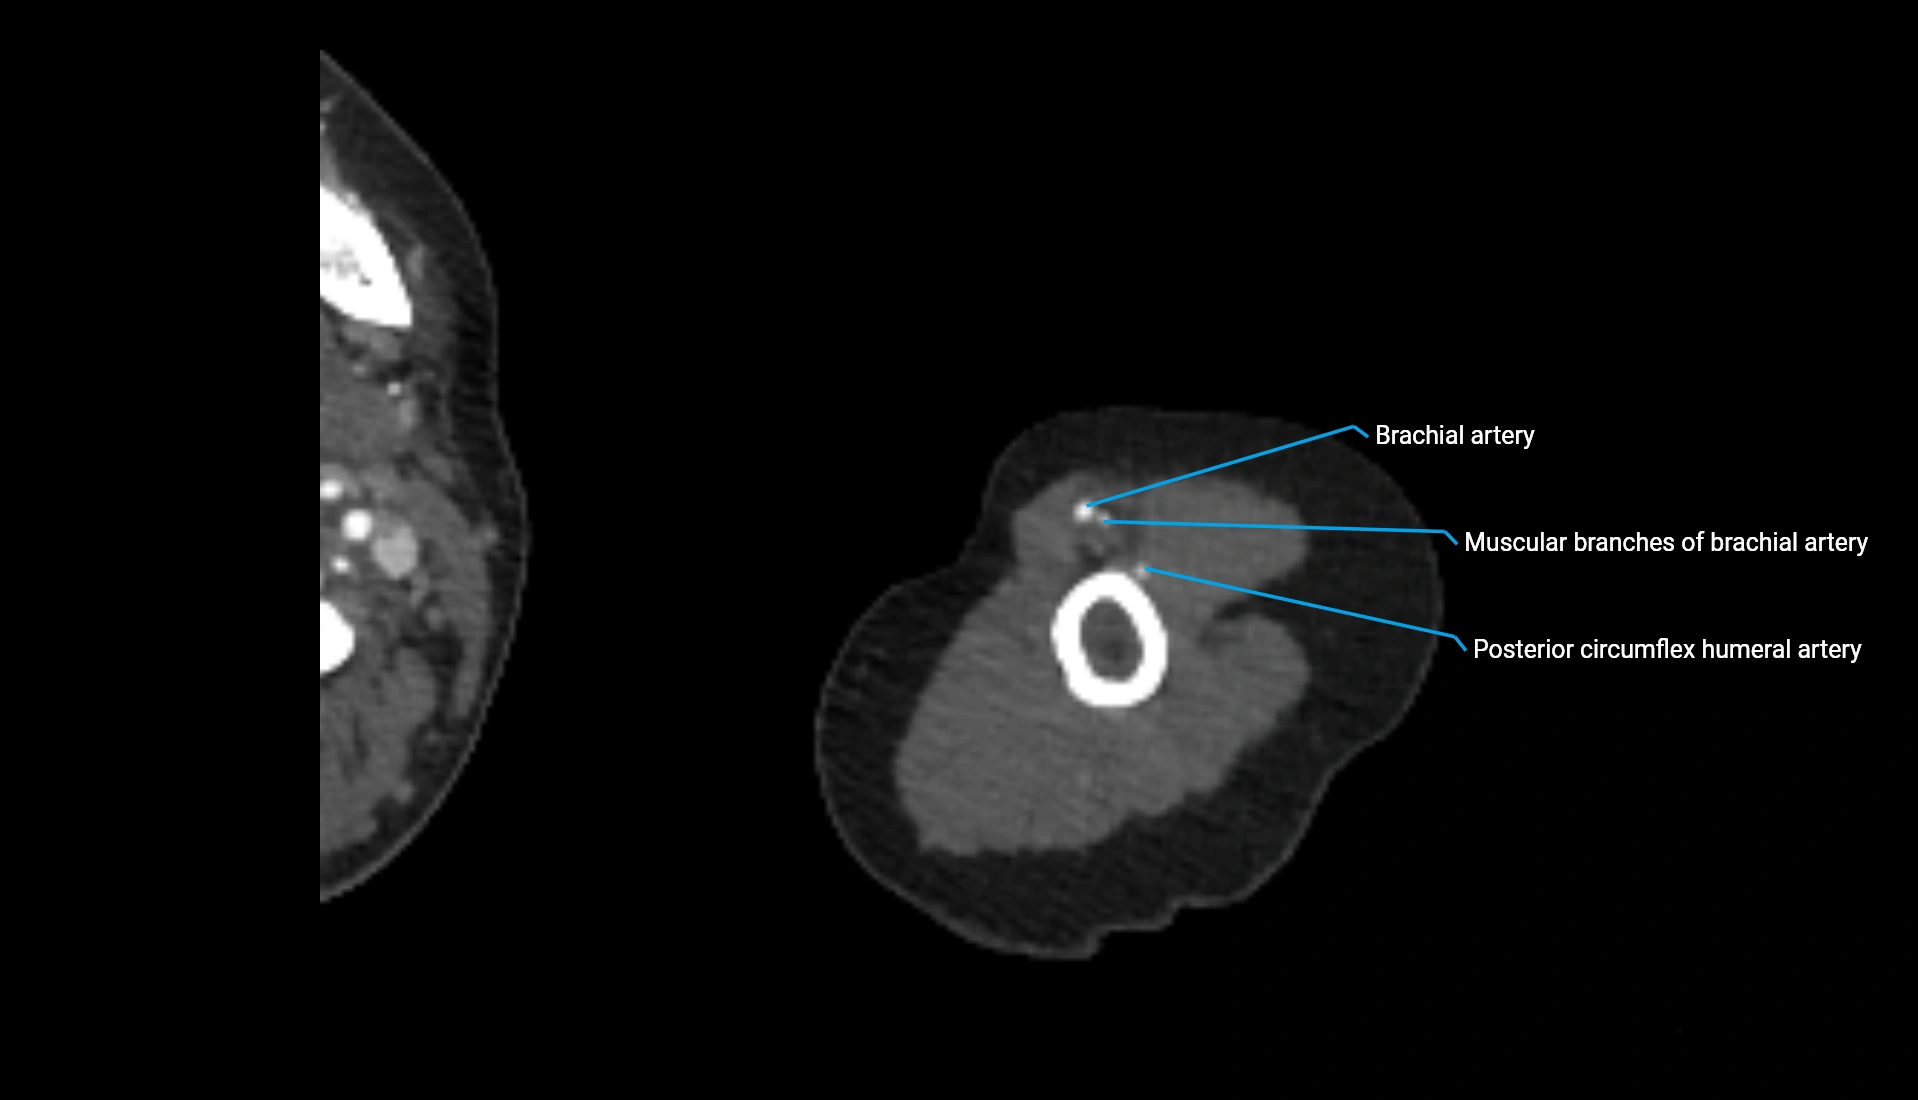

MRI Appearance

T1-weighted images:

• Cortex: Very low signal (dark)

• Subchondral marrow: Bright due to fatty content

• Articular cartilage: Smooth intermediate-to-low signal covering the facet

• Joint fluid: Dark

• Contours: Well-defined curvature matching capitellum